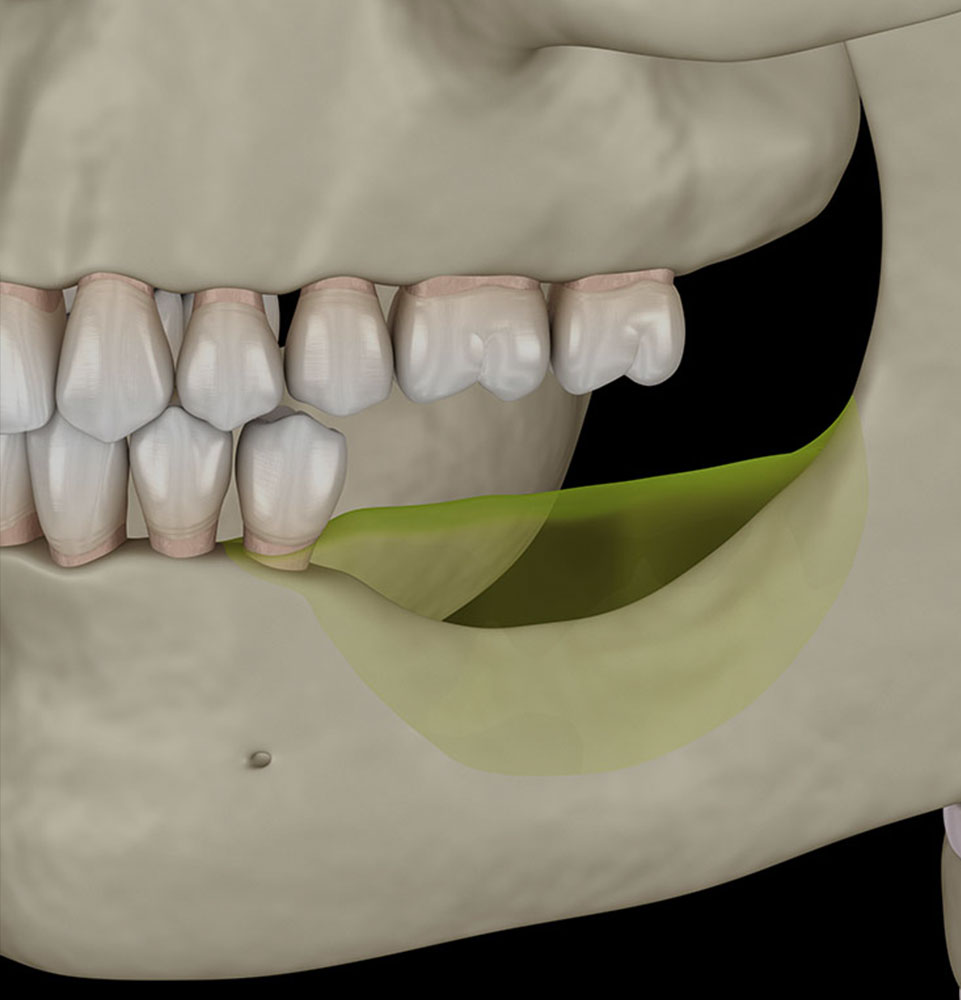

Implant-Supported Overdentures

For patients missing many teeth, implant-supported overdentures offer a secure, affordable alternative to traditional dentures. Anchored on just 2–4 implants, they stay firmly in place, resist slipping, and help preserve bone health. This solution improves comfort, enhances speech, and allows you to eat, chew, and taste food more naturally.